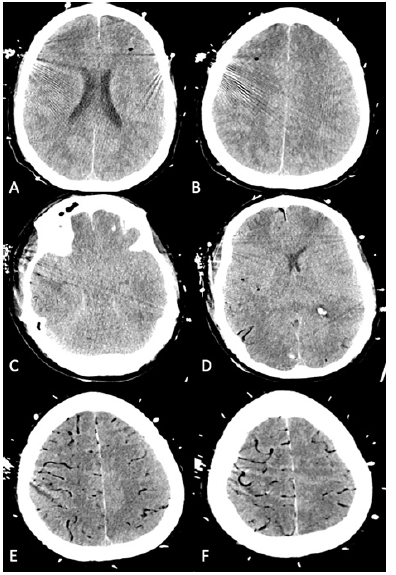

Once therapeutic on heparin, a repeat CT brain was obtained and was notable for multifocal cerebral air emboli with pneumocephalus and surrounding cytotoxic edema (Figure 2 A-B). No clear source for gaseous emboli was detected after evaluation of the ECMO circuit. Repeat CT brain seven hours later revealed markedly worse, diffuse cerebral air emboli with bilateral uncal herniation with diffuse cerebral edema and small right occipital hemorrhage (Figure 2 C-F). The patient was given a bolus of hypertonic saline secondary to diffuse cerebral edema. Previously obtained blood cultures started to grow viridians group streptococcus.

Figure 2:Head CT after ECMO cannulization shows cerebral air emboli Initial axial CT imaging (A, B) shows multiple foci of air emboli with surrounding cytotoxic edema. Repeat axial CT imaging seven hours later shows bilateral uncal herniation (C), right occipital lobe hemorrhage (D) and diffuse vascular air emboli (C, D, E, F)